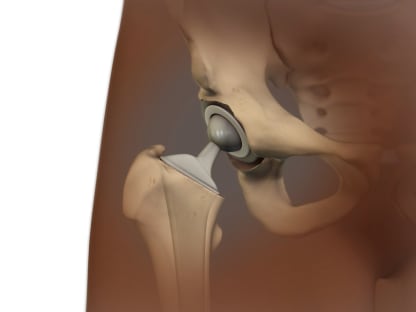

Joint replacement.

This is done when other treatments haven't worked and damage to the joint can be seen on X-rays. It involves surgery to replace the ends of bones in a damaged joint. The surgery creates new joint surfaces. The joints that are replaced most often are the hip, knee, and shoulder. But other joints such as the elbow and the ankle can also be replaced.